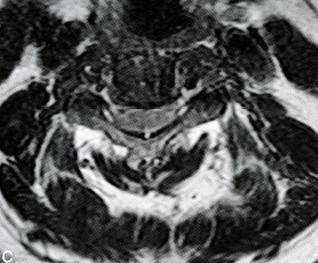

颈椎间盘突出的临床表现及影像诊断,非常详细

318x263 - 14KB - JPEG

375x288 - 18KB - JPEG